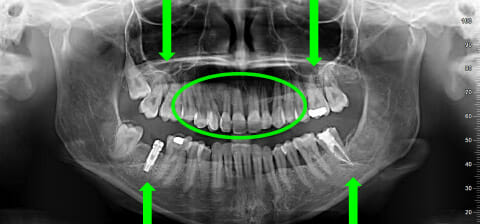

Panoramica prima e dopo la terapia parodontale, ortodontica ed estetica